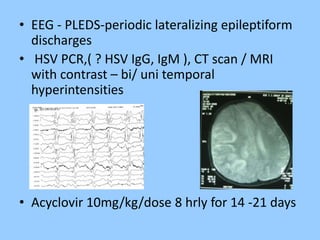

1. The document discusses EEG patterns and findings in various neurological conditions seen in children. It includes descriptions of normal EEG findings as well as abnormal patterns seen in conditions like absence seizures, West syndrome, benign childhood epilepsy with centrotemporal spikes, Lennox-Gastaut syndrome, non-convulsive status epilepticus, subacute sclerosing panencephalitis, and herpes encephalitis.

2. Case studies are presented with clinical histories and EEG findings to illustrate different pathologies. Treatment options are also mentioned for many of the conditions.